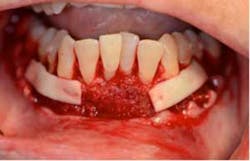

SFOT surgery was performed in the maxillary and mandibular arches with deep buccal corticotomies. Particulate, demineralized, freeze-dried bone allograft and acellular dermal matrix were used to augment the ridges.